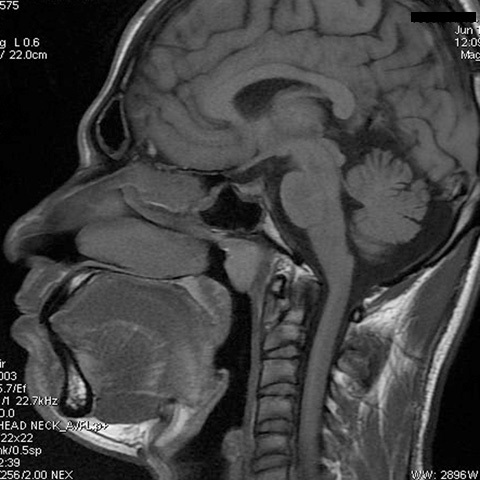

On examination, anterior rhinoscopy and otoscopic findings were normal. Diganostic nasal endoscopy using 00 rigid endoscope [Table/Fig-1] showed a large well encapsulated lesion arising from the posterior wall of the nasopharynx which was covered by smooth mucosa. The lesion was oval shaped, non tender and immobile. Magnetic resonance imaging (MRI) [Table/Fig-2] showed a well-defined oval thick fluid filled cystic lesion measuring 2.2 x 1.6 cm attached to roof of nasopharynx. The lesion was hyperintense on T 1 W images and hypointense on T2 W images.

[Table/Fig-2]:

T1 weighted MRI image showing hyperintense signal

Computed tomogram (CT) scan shows a well-defined midline low density cyst on posterior nasopharyngeal wall. On contrast enhanced CT scan a rim of cyst may enhance but tornwaldts cyst itself remains low attenuation. MRI is now considered the best radiographic imaging study to diagnose the tornwaldt’s cyst as the findings are highly characteristic [8]. On MRI, it may have high signal on both T1- and T2- weighted sequences, presumably because the cyst contains a high concentration of protein, or blood products from prior hemorrhage, or both [10-12]. Post contrast studies usually demonstrate peripheral enhancement of the nasopharyngeal mucosa [8]. Also, it may be hyperintense relative to gray matter on fluid-attenuated inversion recovery images [12].